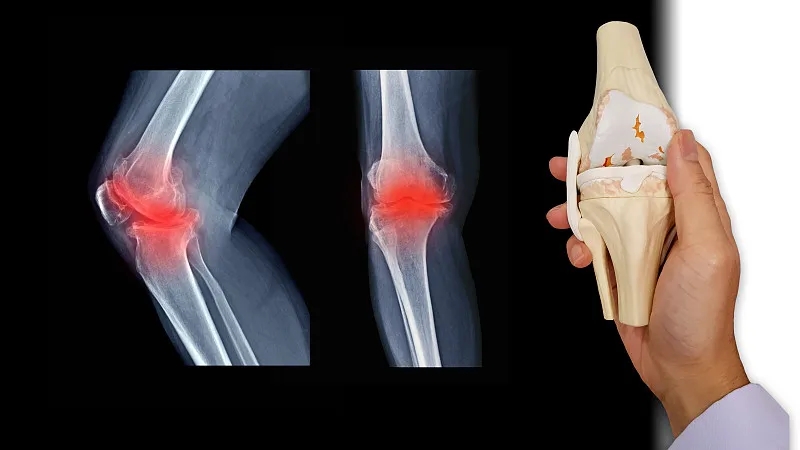

關(guān)節(jié)炎是一個通用術(shù)語,表示關(guān)節(jié)發(fā)炎。骨關(guān)節(jié)炎,俗稱磨損性關(guān)節(jié)炎,是最常見的關(guān)節(jié)炎類型。它與關(guān)節(jié)軟骨的破壞有關(guān),并且?guī)缀蹩梢园l(fā)生在身體的任何關(guān)節(jié)中。它通常發(fā)生在臀部、膝蓋和脊柱的負重關(guān)節(jié)中。它還會影響手指、拇指、頸部和大腳趾。

軟骨是一種堅硬的橡膠狀材料,覆蓋在正常關(guān)節(jié)的骨骼末端。它的主要功能是減少關(guān)節(jié)處的摩擦,起到“減震器”的作用。正常軟骨的減震特性來自其在受壓(壓平或壓在一起)時改變形狀的能力。

骨關(guān)節(jié)炎導(dǎo)致關(guān)節(jié)中的軟骨變硬并失去彈性,使其更容易受到損傷。隨著時間的推移,軟骨可能會在某些區(qū)域磨損,從而大大降低其作為減震器的能力。隨著軟骨退化,肌腱和韌帶伸展,引起疼痛。如果情況惡化,骨頭可能會相互摩擦。

如何診斷骨關(guān)節(jié)炎?

您的醫(yī)生可能會使用X光檢查來幫助確認診斷并確保您沒有其他類型的關(guān)節(jié)炎。X 射線顯示發(fā)生了多少關(guān)節(jié)損傷。如果X射線結(jié)果不能明確指出關(guān)節(jié)炎或其他疾病,則可能需要進行MRI以更好地觀察關(guān)節(jié)和周圍組織。